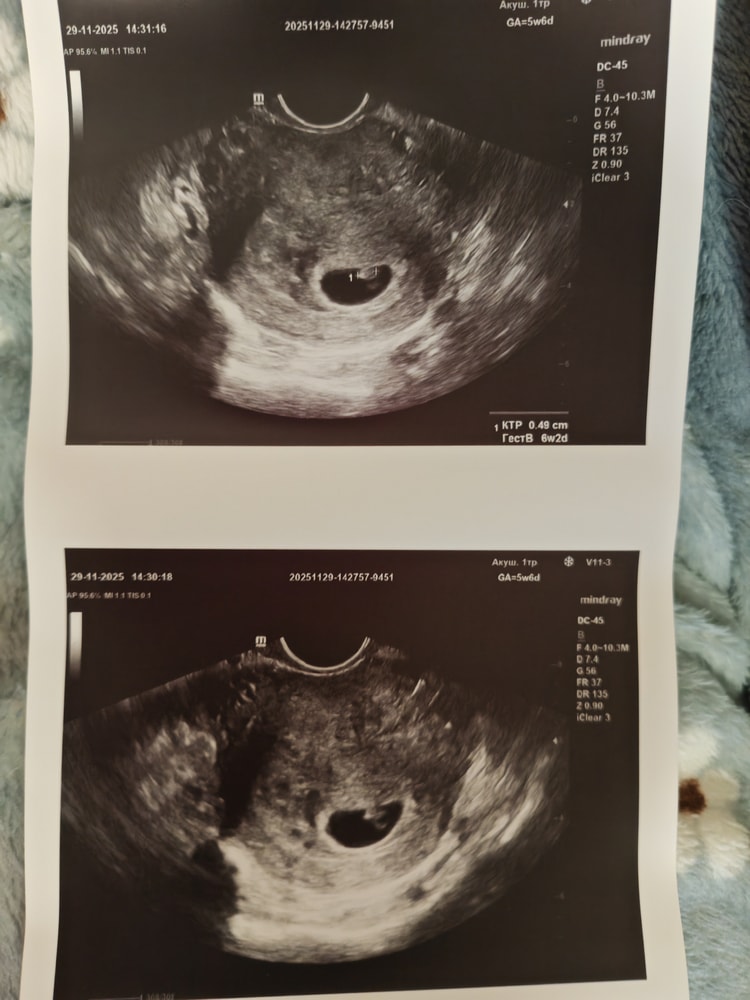

Узи 28 дпп трехдневочки

Девочки, опять реву😭но теперь уже от радости❤️посмотрите пожалуйста, всё ли хорошо?